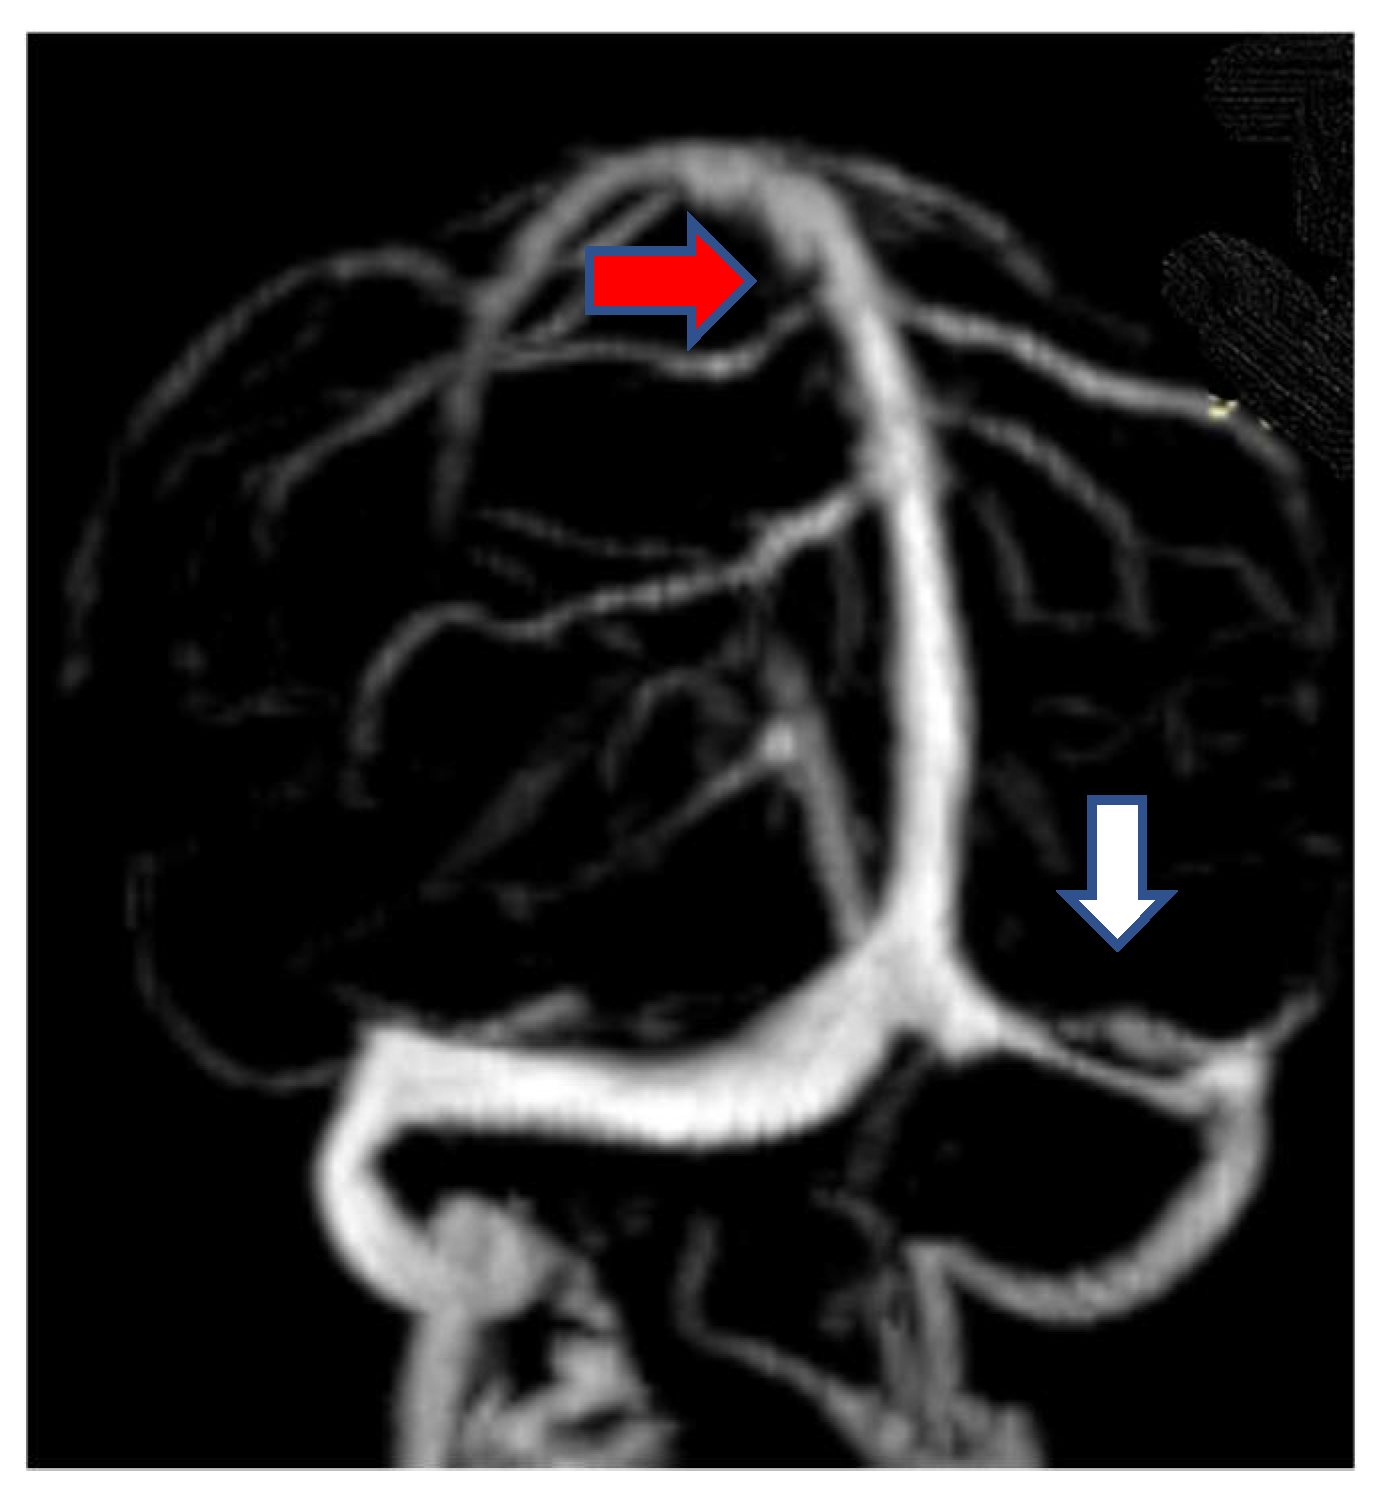

2.1.3. Neuroimaging

- Jianu, D.C.; Jianu, S.N.; Motoc, A.G.; Poenaru, M.; Petrica, L.; Vlad, A.; Ursoniu, S.; Gogu, A.E.; Dan, F.T. Diagnosis and management of a young women with isolated lateral sinus thrombosis. Rom. J. Morphol. Embryol. 2017, 58, 1515–1518. [Google Scholar] [PubMed]